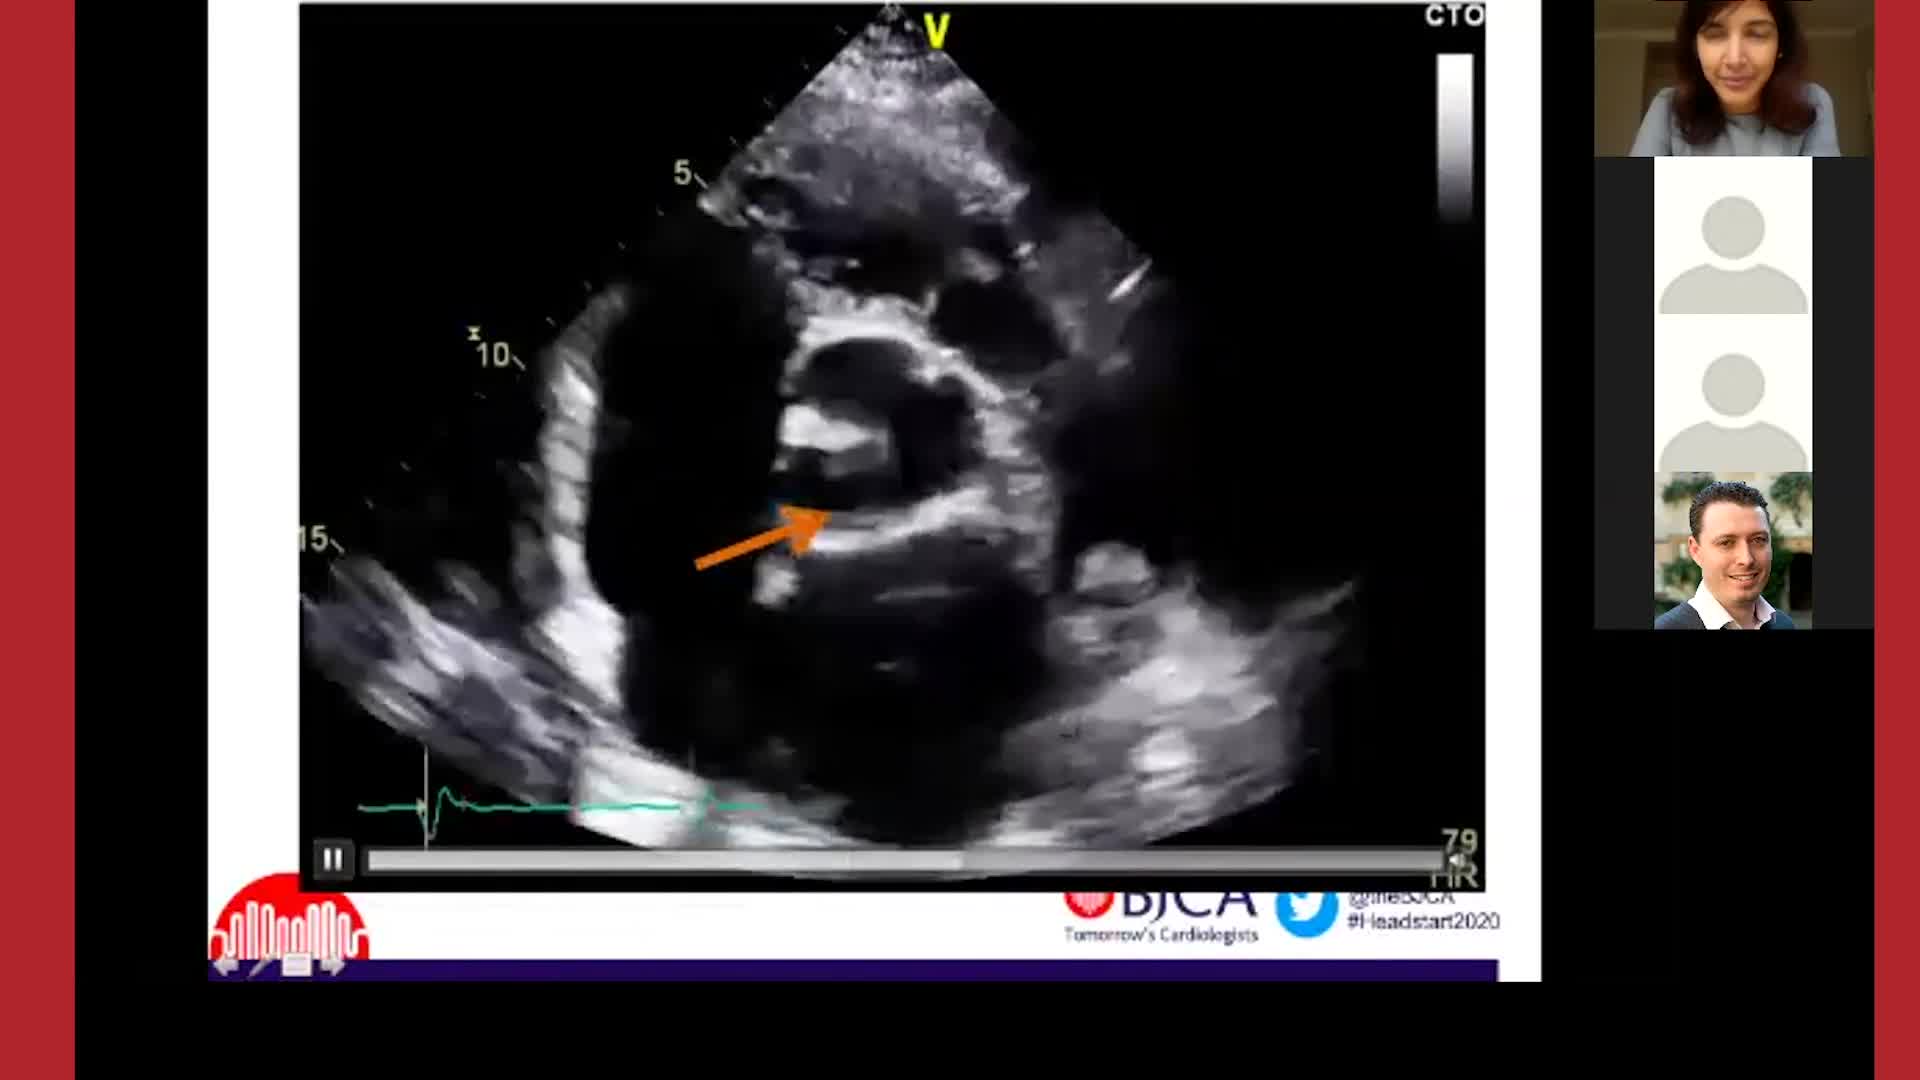

The Comprehensive Valve Center: Who, What, Where and Why?

Join our expert faculty for The Comprehensive Valve Center: Who, What, Where and Why? They will outline what a comprehensive valve center is, who the professionals are there, why these centers are needed, where to access care, and how to ensure that patients are matched to the appropriate therapies. Stay up to date on the latest valvular guidelines, test your knowledge with patient quizzes, and learn on-the-go with podcasts with the Understanding and Managing MR: Evolving Science and Policy online course.